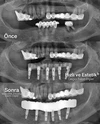

Implant tedavisi